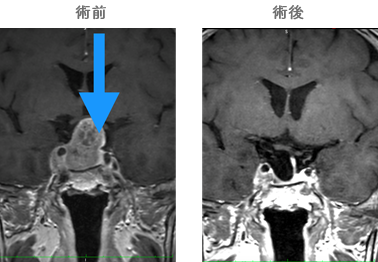

当院で行った手術例

術前(両耳側半盲 黒い部分が見えにくい、視野欠損の部位になります)

術後 症状が回復していることがわかります。